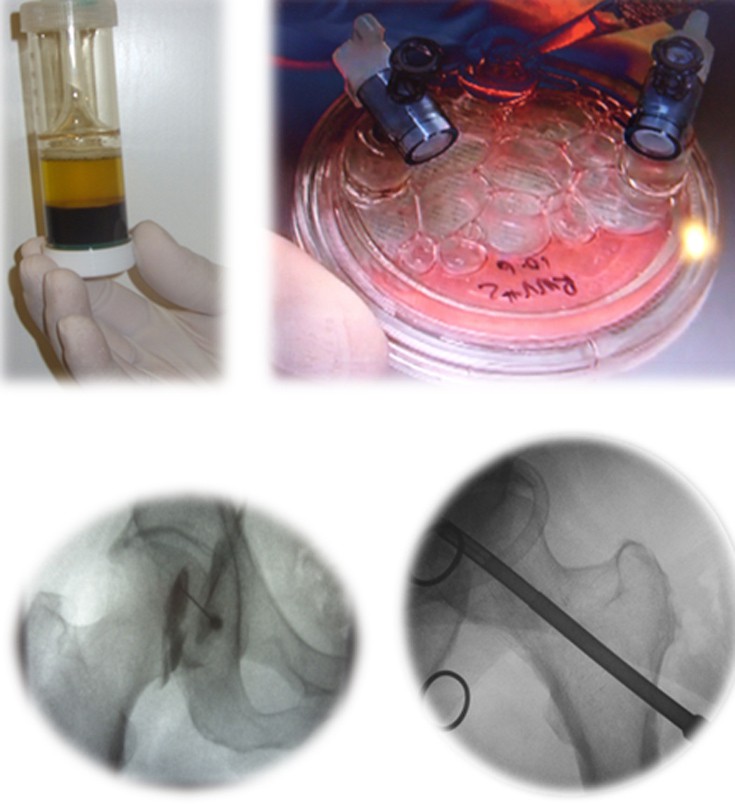

Η οστεοαρθρίτις του ισχίου είναι η κατάληξη όλων των παθήσεων που έχουν ήδη αναφερθεί, δηλ. του συγγενούς εξαρθρήματος, της δυσπλασίας, του CAM, της επιφυσιολίσθησης, του Perthes, της φλεγμονής, του υποκεφαλικού κατάγματος (που διαταράσσει την κυκλοφορία αίματος της κεφαλής), του κατάγματος της κοτύλης, του εξαρθρήματος του ισχίου.